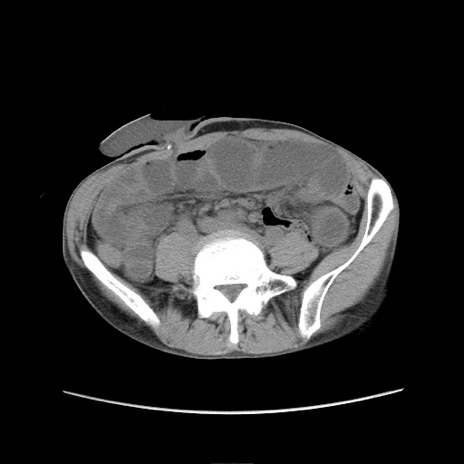

冠状断像

【症例】 60歳代男性

【主訴】 下腹部痛

【現病歴】 本日夜中より下腹部痛の症状認め、受診。

【既往歴】 膀胱癌(膀胱全摘+尿管皮膚瘻術) 、胃癌術後

【身体所見】 BT 35.3℃、PR 58/min、BP 136/98mHg、腹部平坦、軟、腸蠕動音±、ストマ留置あり、左上腹部~正中部に圧痛あり、反跳痛なし。

【データ】WBC 5100、CRP0.01